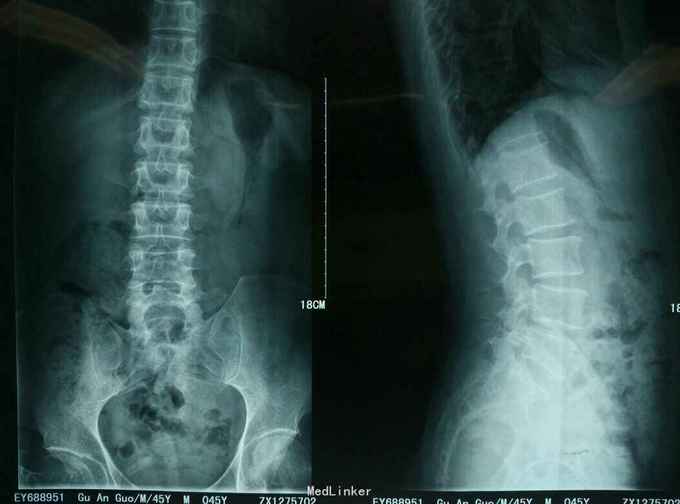

患者,男,42岁,因“左下肢疼 痛麻木一个月”入院。一个月前有搬重物的病史。

查体:L45间隙压痛,左侧小腿外侧及左足拇趾感觉减退,左下肢肌力四级,左侧下肢直腿抬高试验30度阳性。腰椎MR提示: L4/5椎间盘脱出向上高度游离,压迫左侧神经根。

诊断:L45腰椎间盘脱出游离。 治疗:行侧路椎间孔镜手术。